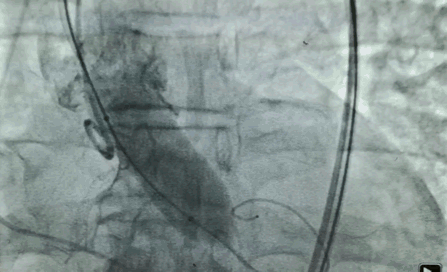

70岁女性,梅毒合并二叶瓣,主动脉瓣狭窄,肺部有肿瘤。

由于有梅毒阳性,根据传染病防治法的要求,这例病人被放在了最后。